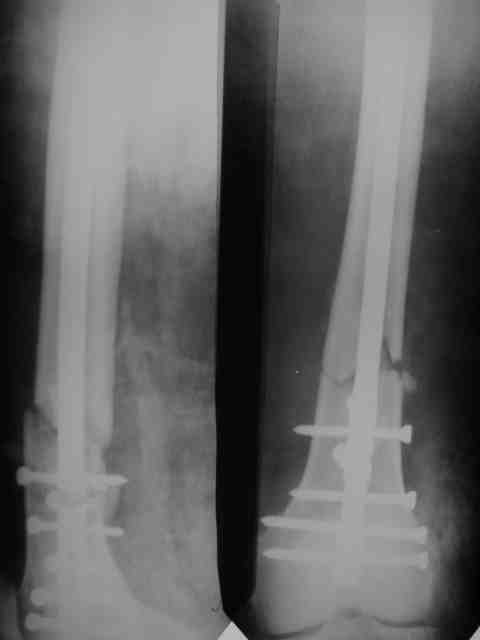

Поступил дядя 54 лет.Дорожная травма 14.10.2006

К нам попал на 11 сутки.Вроде как согласился на ретроградный штифт "Санатметал", но отказался!

Выполнили вот такой остеосинтез (вариант гаражной ортопедии - Александр Николаевич знает) модифицированным штифтом ЦИТО.

Есть сомнения в жесткости конструкции!

Обсуждается вопрос брейса-есть ли смысл?

P.S.Поллер винт внизу реально помог - сложность была (оперировали на 17 сутки)